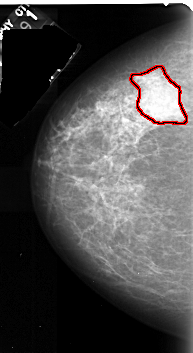

A_1036_1.RIGHT_CC

LEFT_CC LINES 5281 PIXELS_PER_LINE 2881 BITS_PER_PIXEL 16 RESOLUTION 42 OVERLAY

FILE: A_1036_1.LEFT_CC.OVERLAY

TOTAL_ABNORMALITIES 1

ABNORMALITY 1

LESION_TYPE MASS SHAPE IRREGULAR MARGINS ILL_DEFINED

ASSESSMENT 4

SUBTLETY 5

PATHOLOGY MALIGNANT

TOTAL_OUTLINES 1

BOUNDARY